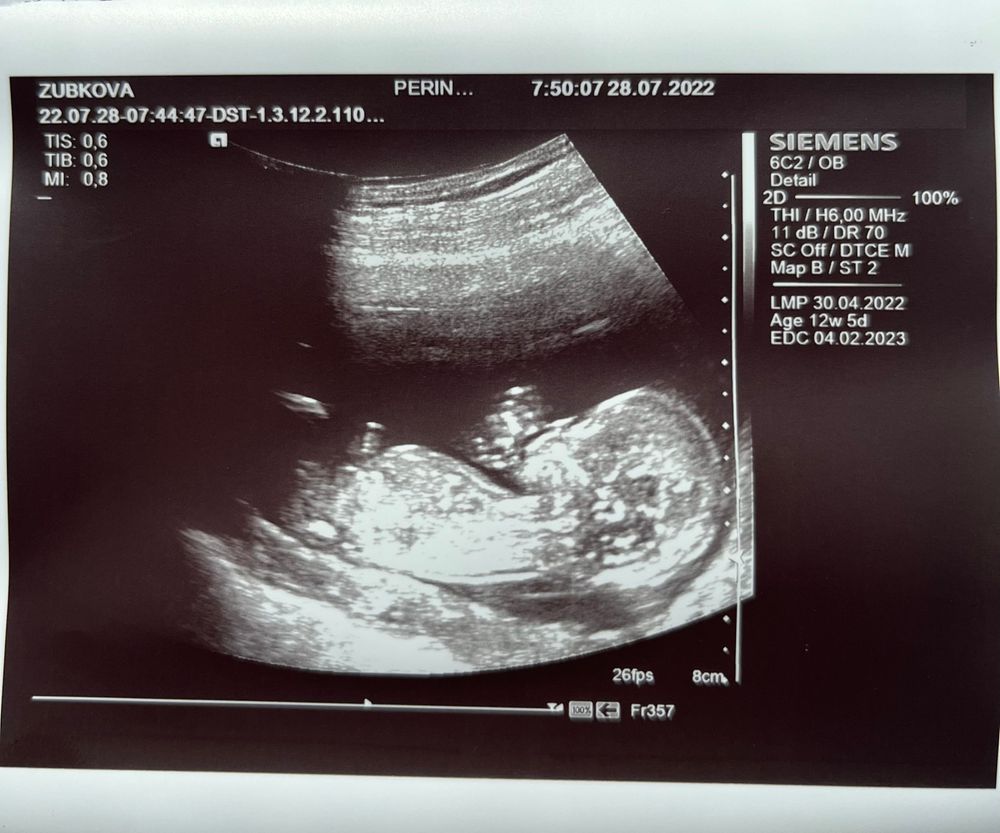

Сегодня был первый скрининг… по узи все хорошо; первый раз выдохнула; теперь жду результат крови, надеюсь так же выдохну!

И впервые услышала сердце- непередаваемые ощущения… так странно что у тебя внутри кто-то растёт 😁

Как здорово!!!! 😊 какой уже большой малыш на фото😁 у меня тоже скоро такой будет на скрининге🙌🏼 Легкой беременности Вам!!!🌼